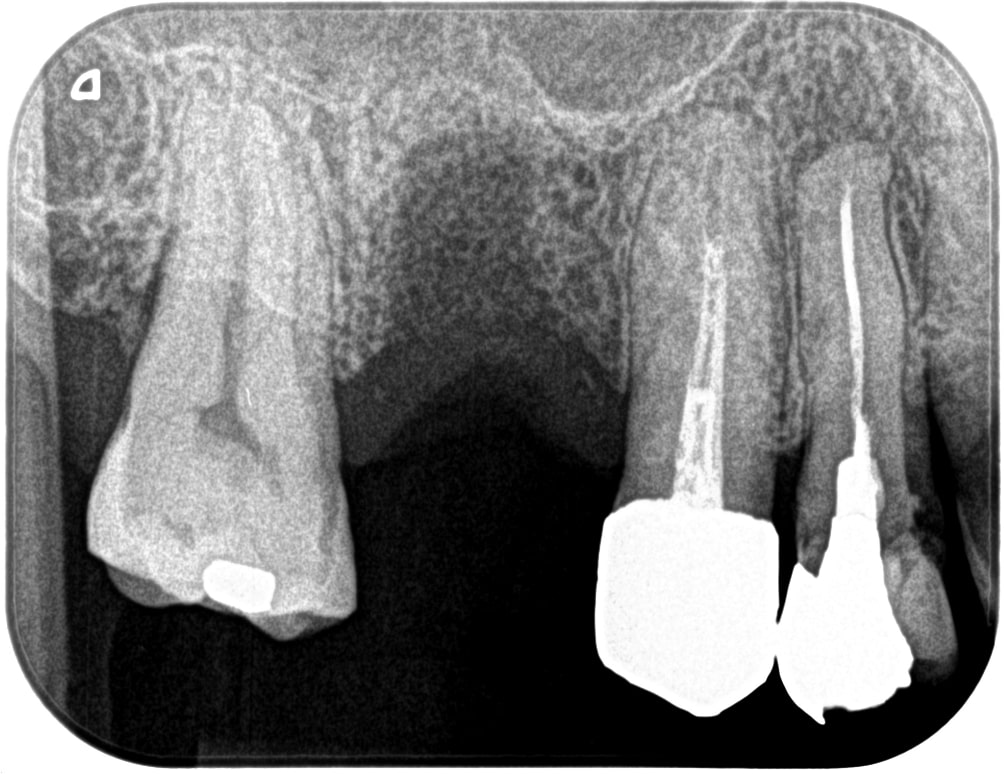

症例470代 女性 主訴 右奥歯がグラグラして噛めない

治療前

治療後

治療前

治療後

右上小・大臼歯部は、残存骨が1~2㎜程度しかないので、ソケットリフト(上顎洞洞底膜挙上術)を適用。

約5ヶ月間の治療期間を経て、ジルコニアを装着し終了。

リスクとしては外科的侵襲がある。デメリットは、保険外診療の為、経済的負担がある。

費用 126万(税込)(オペ・仮歯・最終補綴物まで含む)